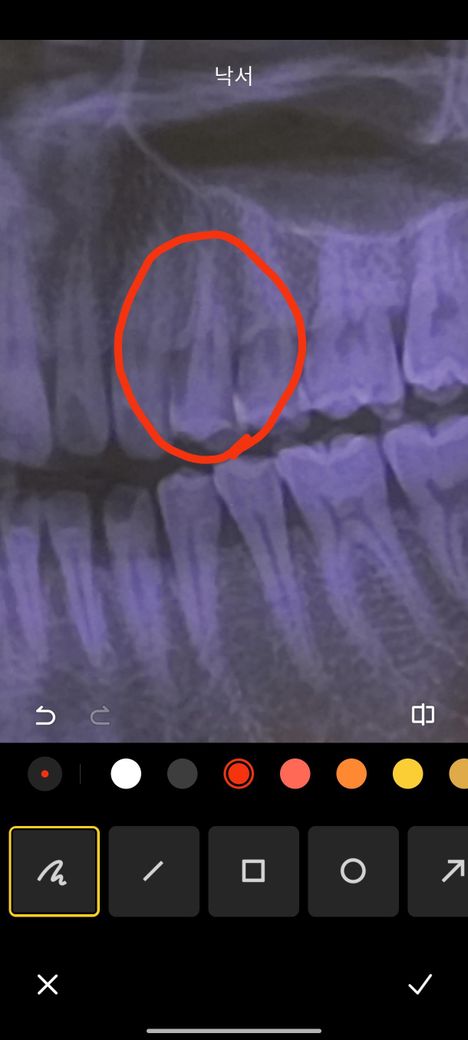

사진은 충치치료전 치과두곳에서 엑스레이 찍은건데

동그라미 친 부위만 건드리면 찌릿찌릿 넘아프고 안건드려도

쑤시는 느낌이 들어요 사진보시고

해당 엑스레이 사진은 해상도가 떨어져 정보가 제한적입니다.